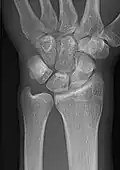

- Wrist - DP and Lateral

-

Left wrist by dorsoplantar projection -

Lateral projection

- Scaphoid - DP with Ulna deviation, Lateral, Oblique and DP with 30° angulation